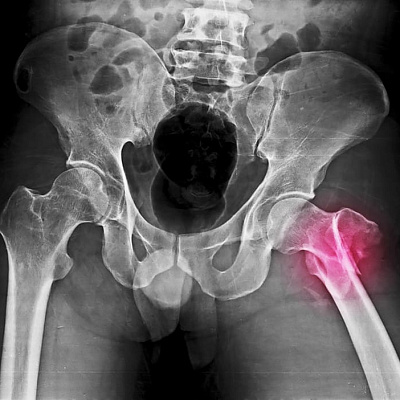

Врожденные вывихи сопровождают человека с момента появления на свет. Наиболее часто страдает тазобедренный сустав (при пресловутой дисплазии, которая достигает более развитой формы, степени тяжести). Реже вовлекаются колени, верхние конечности.

- вывихи ноги (также представлены несколькими подвидами: вывихом бедра, вывихом голеностопа, вывихом стопы, вывихом надколенника и более тяжелым вывихом коленного сустава).

Вывихи коленной чашечки, вывихи лодыжки и вывихи тазобедренного сустава вместе с нарушением положения челюсти встречаются особенно часто. Травмы локтевого сустава, колена встречаются реже.